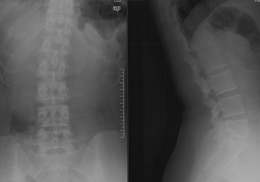

腰椎MRI示:L5S1椎间盘突出,左侧神经根受压。

(图)术前X线片